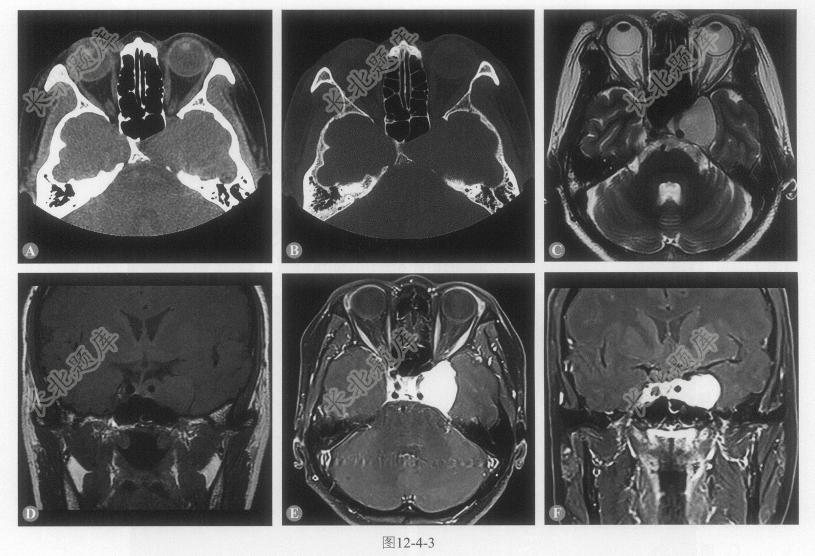

- 多项选择题1.患者的影像学表现包括:

A、左侧鞍旁、鞍内见类圆形T

WI低信号、T2WI高信号影,边界清楚,信号均匀B、无明显占位效应及周围水肿

C、增强呈明显均匀强化,见“脑膜尾征”

D、邻近骨质呈压迫吸收改变

E、病变累及左侧Meckel腔